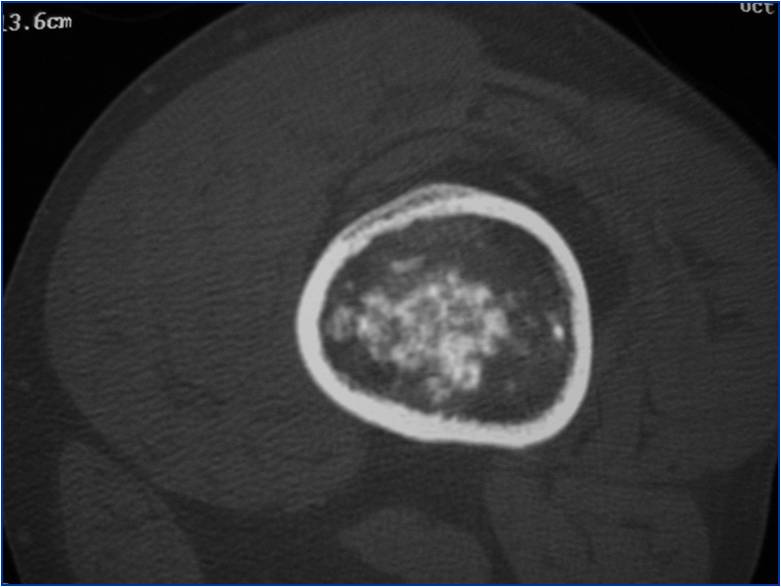

- Localized, radiolucent defect usually with punctate calcifications

- Calcifications are typical but not always present

- Matrix may demonstrate various degrees of calcification

- Calcifications are stippled, punctate, popcorn like calcifications and “Ring and Arc” calcifications

- Cartilage tumors grow in a lobular manner. The perimeters of the lobules undergo

- enchondral ossification that may calcify. If the entire perimeter of the lobule calcifies it appears

- radiographically as a “Ring”. If a portion of the perimeter of a lobule calcifies it forms an “Arc” on

- an X-ray.

- Chondroid matrix with calcifications in majority of tumors

- Approximately 20% have limited or no calcifications